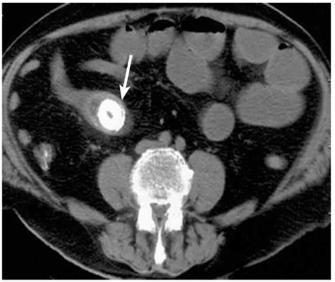

לעתים רחוקות, כדי לקבוע את גובה החסימה ואת מידתה בחולים הלוקים בחסימה דינמית, או כדי להבדיל בין שתי צורות החסימה, יש לצלם את החולה לאחר בליעת חומר ניגוד נספג מסוג גסטרוגרפין. בחסימה דינמית ניתן למצוא התקדמות של חומר הניגוד עד לחסימה (תצלום 6.4), ואילו בחסימה אדינמית ניתן למצוא אמנם מעבר לכל אורך המעי, אך מעבר איטי ביותר. לחולים שבהם יש חשד לחסימת הכרכשת, אין לתת בריום דרך הפה אלא לבצע חוקן בריום תחילה. ב- CT בטן עם חומר ניגוד ניתן לראות לולאות מורחבות שלאחריהן לולאות התמט, בצקת של הלולאות ונוזל ביניהם (תצלום 7.4).

בחולים הלוקים בחסימת מעי על-ידי אבן מרה החודרת למערכת העיכול אפשר להדגים את החסימה בעזרת חומר ניגוד (תצלומים 8.4 ו-9.4) או ב-CT (תצלום 10.4). בחולים הלוקים בחסימת מעי על-ידי פיטובזואר להדגים את החסימה בעזרת חומר ניגוד (תצלום 11.4) או ב-CT. התפשלות של המעי ניתנת להדגמה בצילום בריום או בטומוגרפיה ממוחשבת (CT) (תצלום 12.4 - 13.4)